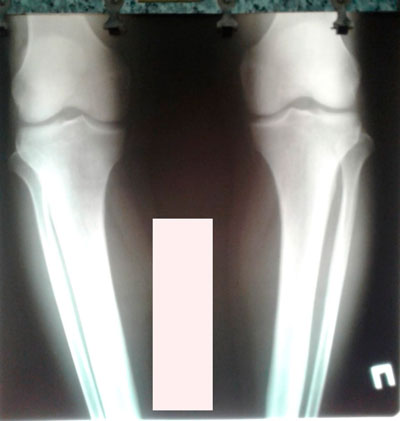

Исходник - 40 лет.

Дата операции - 22.06.2019г.

Рентген в 92 дня